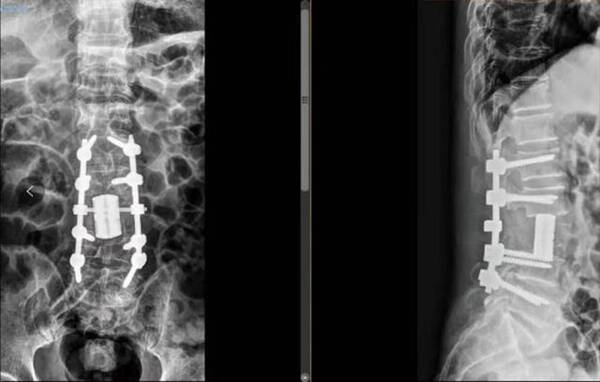

MRI顯示:L3椎體被腫瘤完全破壞,右側(cè)神經(jīng)受壓明顯。

3D打印術(shù)后人工椎體植入脊柱重建良好。